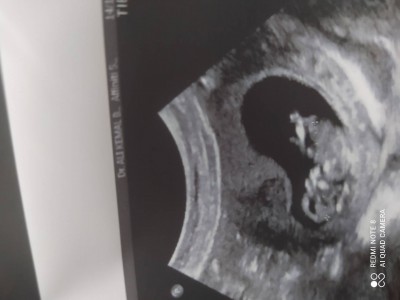

Kizlar 15+4 oldum ama cinsiyet tahmini bile etmeye gerek duymayan cokkk rahat bir doktora denk geldim doğunca nasılsa gorursun kalk hadi diyor yeminle kafasını duvara vurasim geliyor zaten benim morel sıfır oluyor hadi bi bakin tahmin edin

Gebelik haftası 15+4

Erkeğe benziyo gibi ama bnde doktorunu değiştir morelini bozma o doktordan bı hayır gelmez

Erkeğe benzettim bende

He ya biz bilmiyoduk doğunca ogrenecegimizi ne kadar sinir bozucu ya rabbim gönlündekini nasip etsin canım kiza benzettim ben

kiz canım kız

Erkek gibi sanki icimede öyle doğdu ama kesinlikle doktorunu değiştir o ne demek mis öyle şaka yaomis bile olsa en sonunda sana cinsiyetini söylemesi lazım bazen şakacı doktorlar oluyor benim doktorum gibi mesela  ama  hiç öyle birşey duymadım yani

Erkege benziyor sanki bence doktorunuzu degiştirin sonra sıkıntı yaşamayın derim